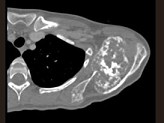

男,27岁,左肩部扪及一硬结1月余,有轻压痛,结合影像学检查,最可能的诊断是()

• A.骨肉瘤

• B.骨软骨瘤

• C.骨巨细胞瘤

• D.尤文肉瘤

• E.骨囊肿